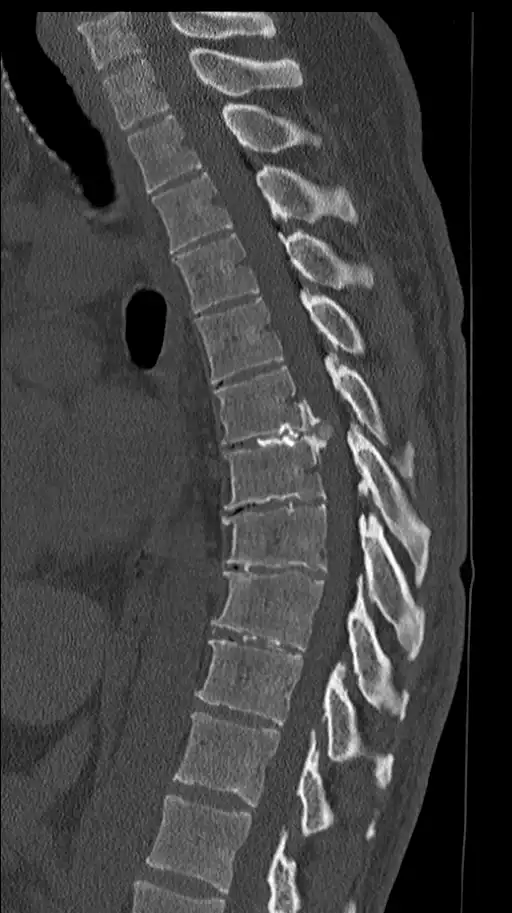

Entre as vértebras da coluna existem os discos intervertebrais, estruturas que funcionam como amortecedores naturais. Eles absorvem impactos, distribuem cargas e permitem a mobilidade da coluna. Quando esse disco sofre desgaste, fissuras ou deslocamento do seu conteúdo interno, ocorre a hérnia de disco.

Dependendo da localização e da intensidade, a hérnia pode comprimir raízes nervosas próximas, provocando sintomas neurológicos.